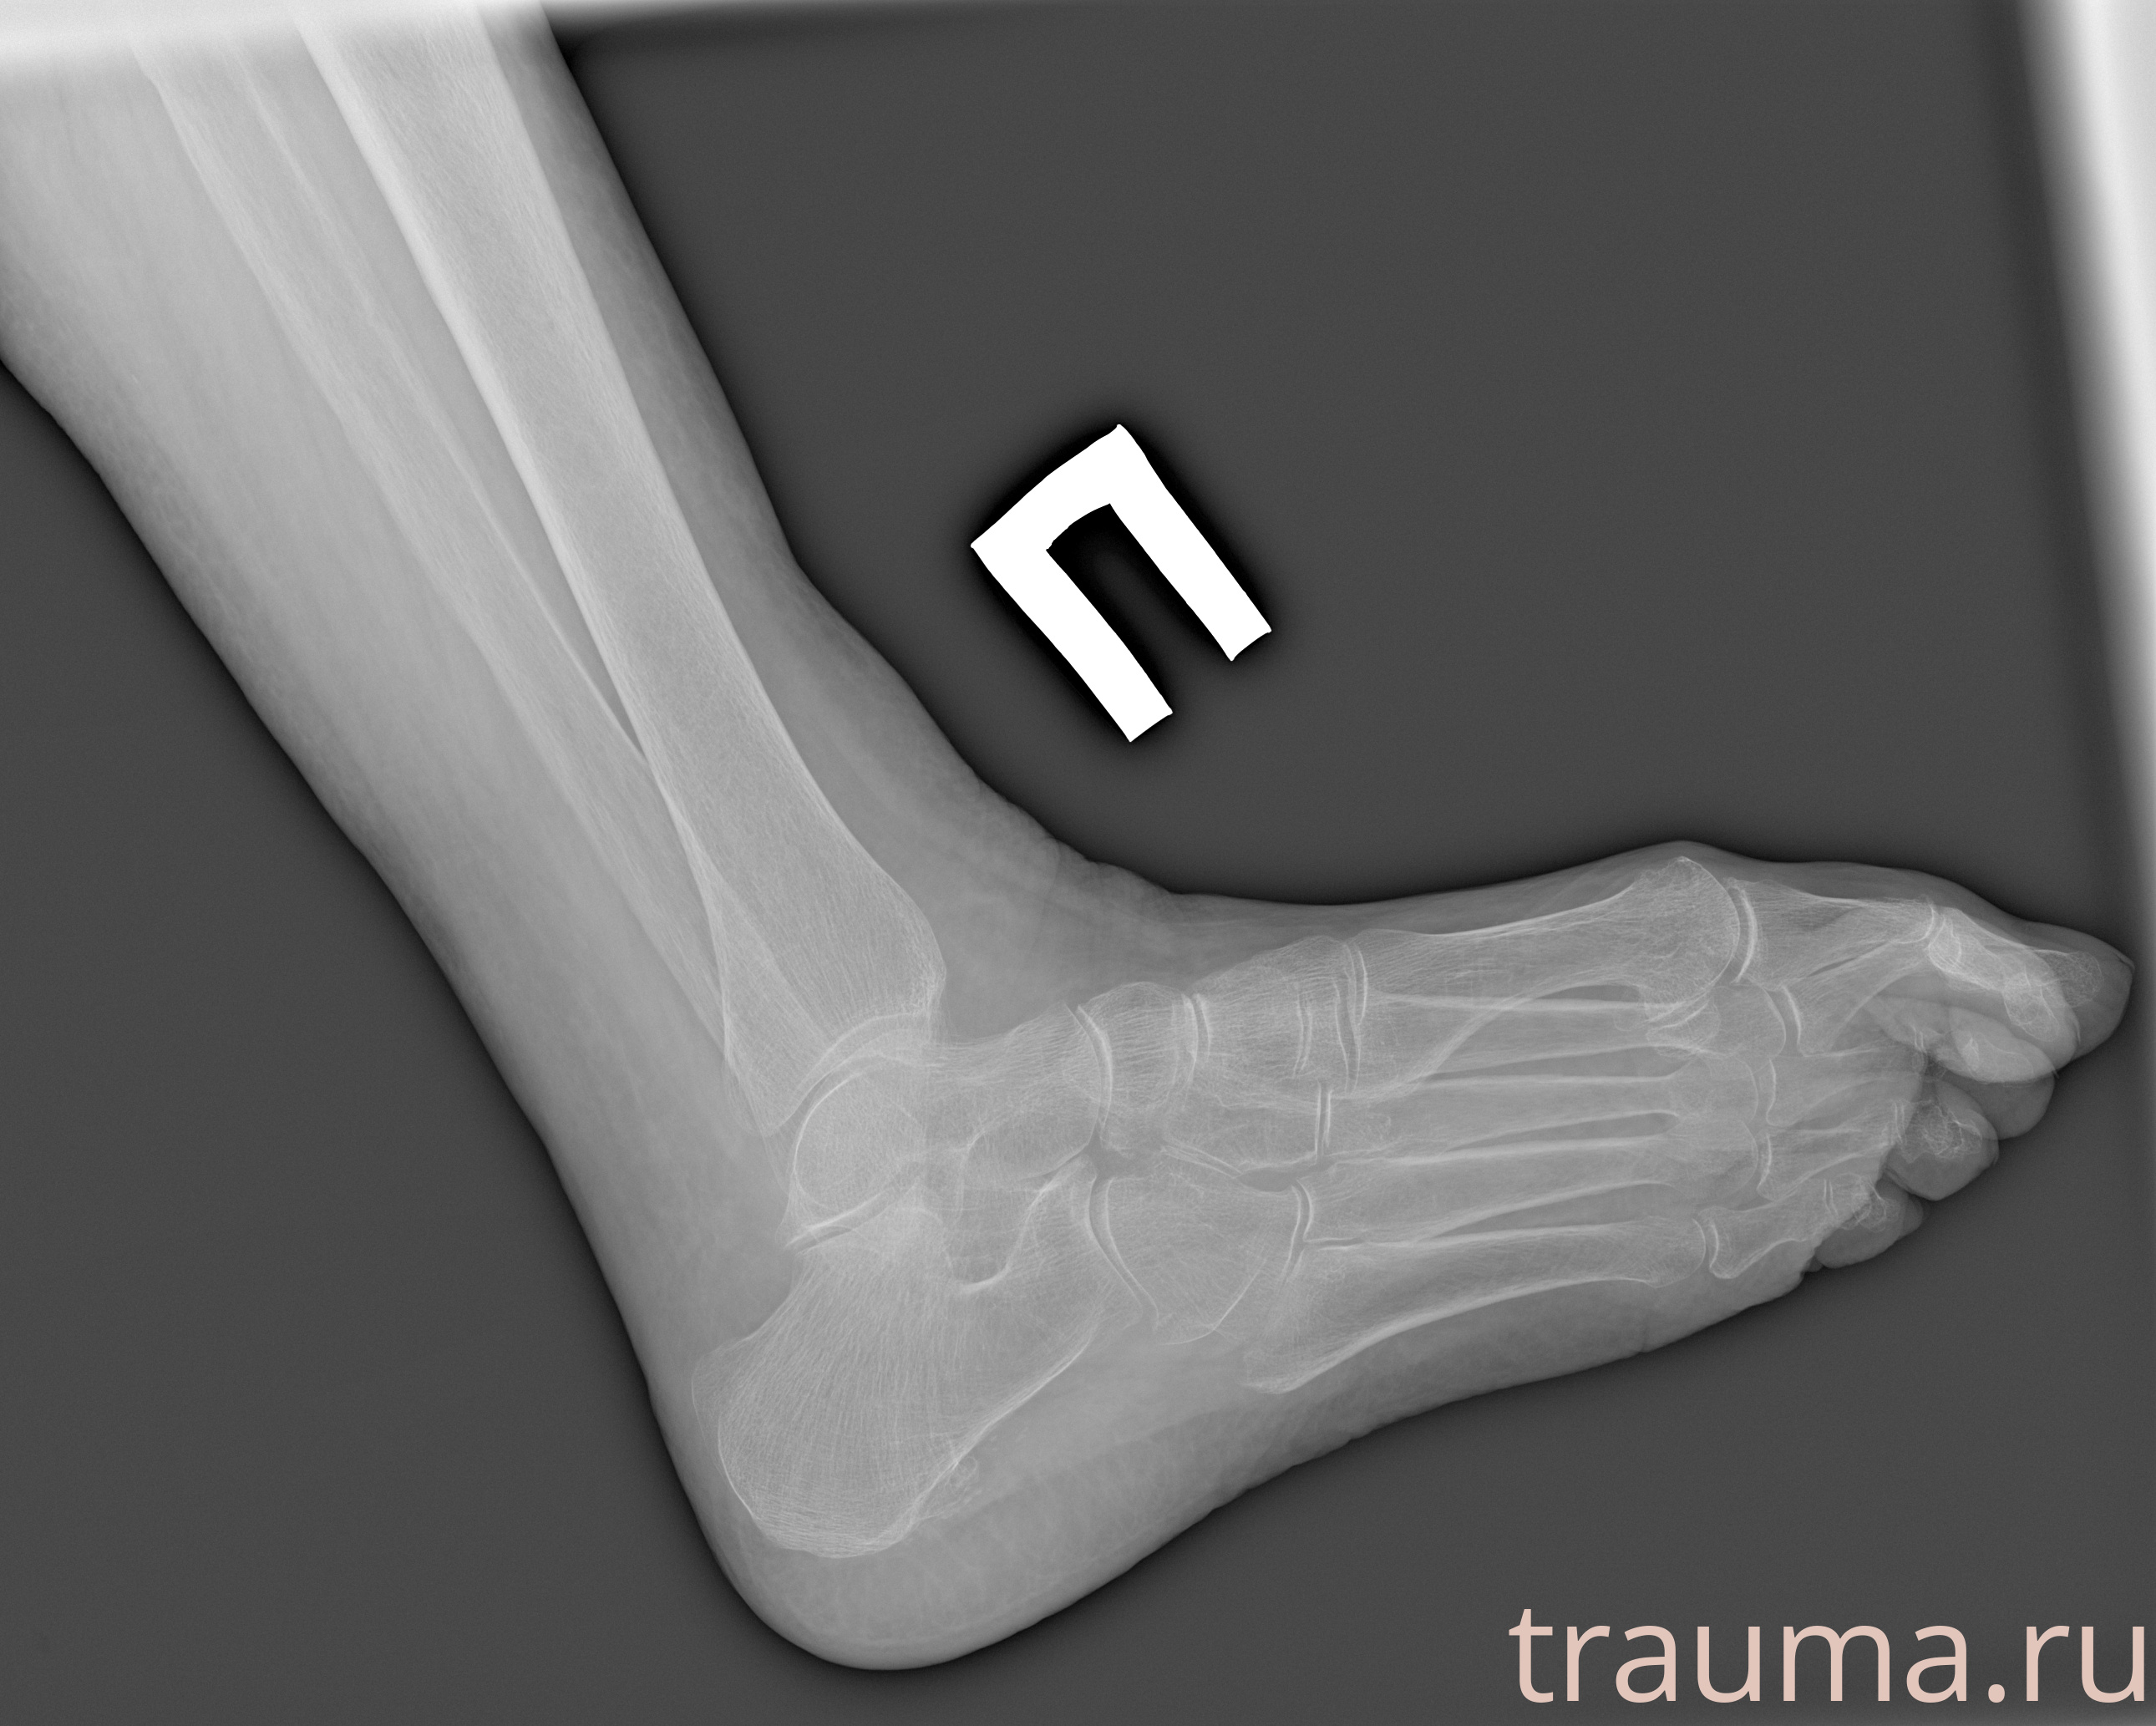

Рентгенограммы

Рентген на дому: по вашему адресу приезжает врач-рентгенолог, травматолог-ортопед с мобильным рентгеновским аппаратом, проводит диагностику травмы или заболевания, делает необходимые рентгенограммы, дает рекомендации по дальнейшему лечению. Получить качественные снимки в домашних условиях возможно благодаря уникальной методике, разработанной МосРентген Центром для института  Склифосовского